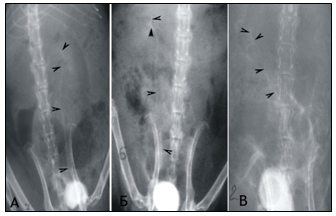

Voiding cystography was performed at 1, 3, and 6 months of the experiment, by injecting 3-5 ml of urographin into the cavity of bladder using a syringe. At the 6th month of the experiment, the levels of TGF-β1, Ang II in the urine of animals were determined by ELISA and recalculated per mmol of creatinine determined in a specific urine portion (ng/mmol of creatinine). Removal of animals from the experiment was carried out after anesthesia by intraperitoneal administration of 0.4 ml of 5% ketamine. Morphological studies were performed by macro- and microscopy of the renal-ureteral complexes obtained from individuals of the experimental groups and the control group. The material for histopathological research was biopsy specimens (1x1x0.5cm) of the renal-ureteric complex obtained at necropsy of animals, previously fixed in 4% and 10% formalin solution for no more than 12 hours. Histopathological processing of material in biopsy specimens was carried out according to standard protocols of histological technology using routine (hematoxylin-eosin - GE) and special (picrofuksin according to Van-Gizon (VG), aniline blue according to Mason) coloring methods. The collection of material from rats of the control group was carried out in dynamics simultaneously with experimental animals (1 rat in 1, 3 and 6 months).

Figure 1 Сystography in rats. Cystic ureteral reflux of the III degree at the 6th month of the experiment: A) on the left in the individual of the 1st group; B) on the right of the individual 2 groups.